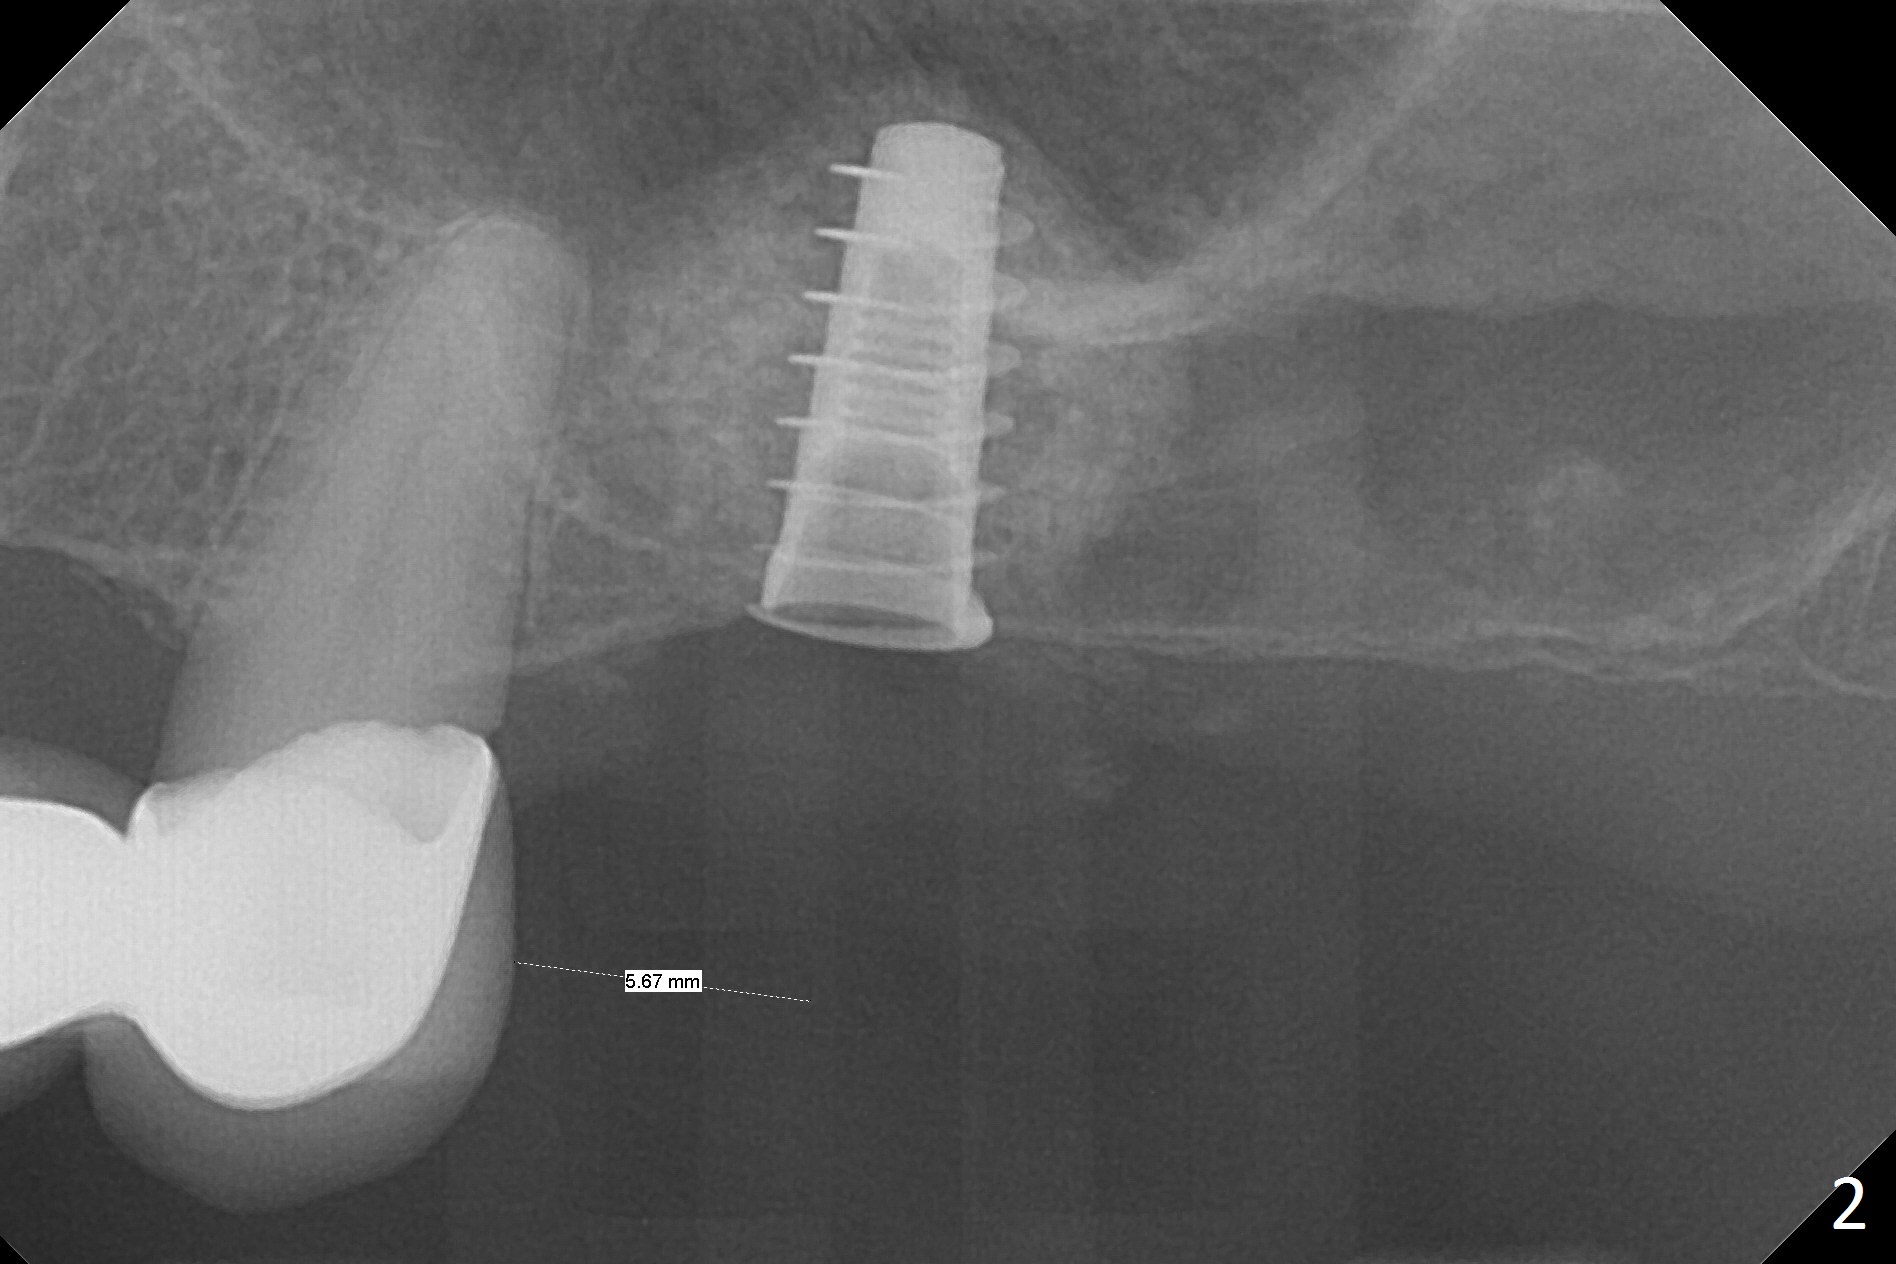

Blood drawing for PRF fails. After NO inhalation and local anesthesia, an incision is made at the narrow ridge of #14. Magic Sinus Lifter is used to elevate the sinus floor for ~ 5 mm, followed by insertion of allograft/Osteogen and 4.0x11 mm dummy implant partially (Fig.1). With approximately 10% more of graft being placed, a 4.5x9 mm IBS implant is placed with insertion torque of 15 Ncm (Fig.2). The shape of the sinus suggests that the primary stability is derived from the contact between the implant and the sinus floor (Fgi.3, preop CBCT coronal section). Approximately .5 mm implant threads are exposed buccodistopalatally, which are covered by allograft and collagen membrane before suturing. There is one episode of nasal discharge postop. The wound dehisces without sign of infection (Fig.4 (1 month 1 week postop)).